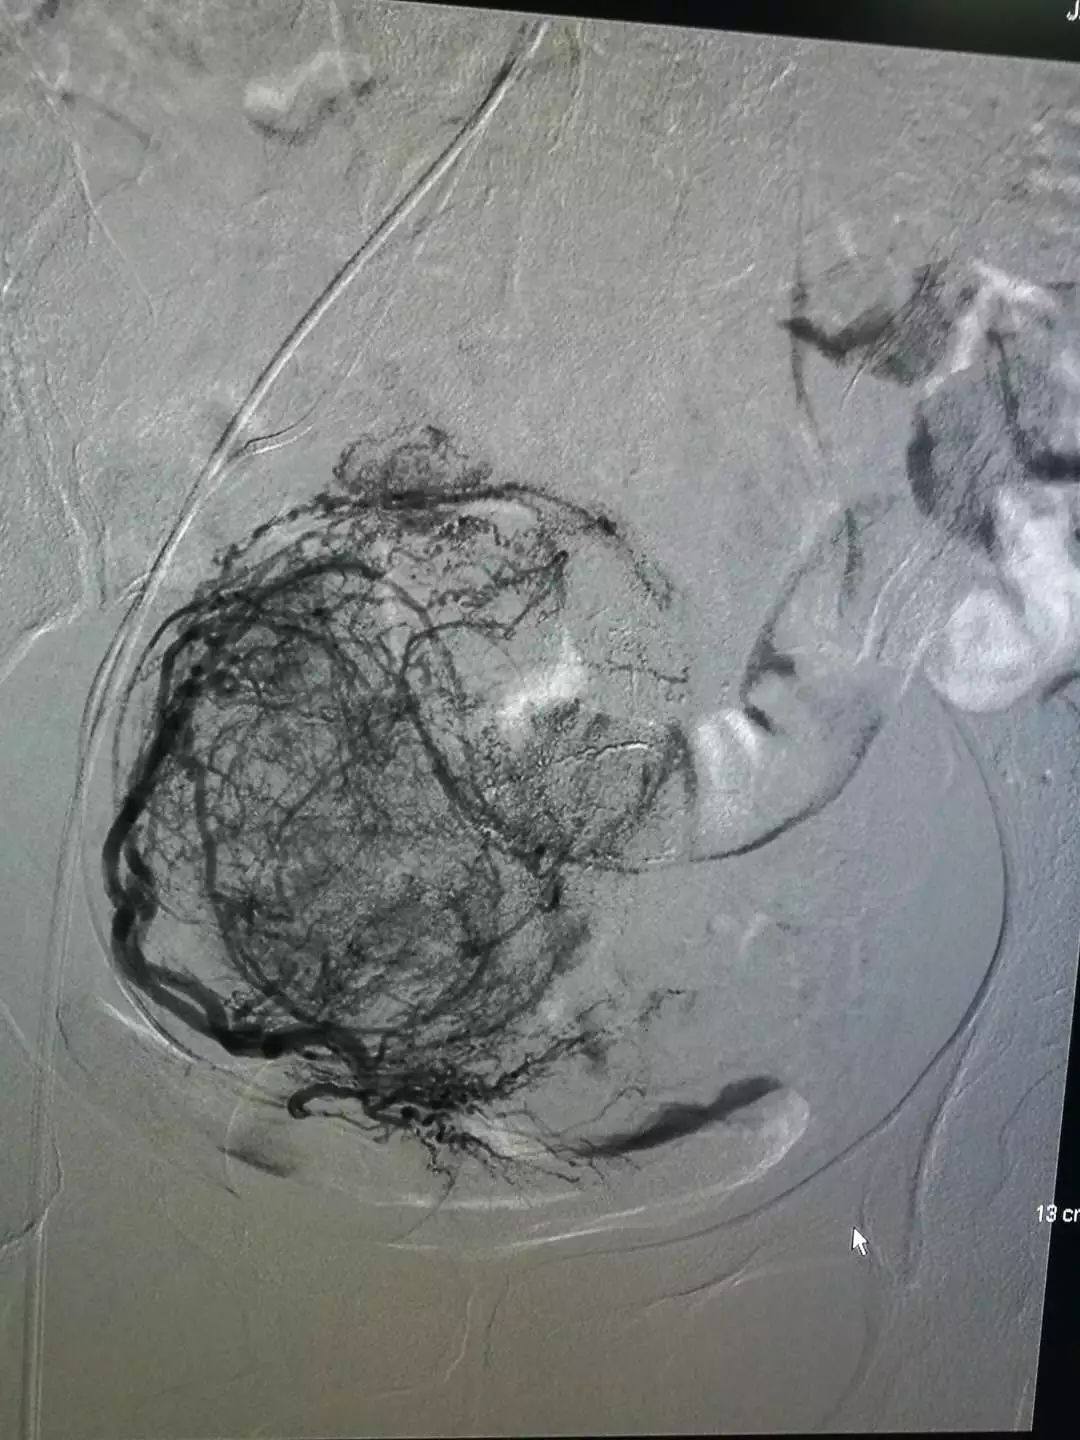

介入栓塞后的碘油沉积

介入栓塞治疗后碘油沉积